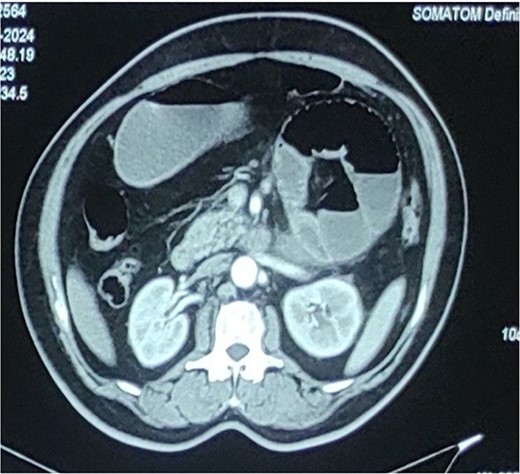

An abdominal X-ray showed distended small bowel loops with multiple air-fluid levels (Fig. 1). A CT scan of the abdomen and pelvis revealed multiple distended jejunal loops (maximum diameter 5.6 cm) clustered in the left upper quadrant, with proximal and distal narrowing suggestive of a closed-loop obstruction, consistent with a paraduodenal hernia (Fig. 2).

Computed tomography abdomen and pelvis showing distended multiple jejunal loops bunched together in the left upper quadrant with narrowing of both proximal and distal ends suggestive of closed loop obstruction (? Paraduodenal hernia).